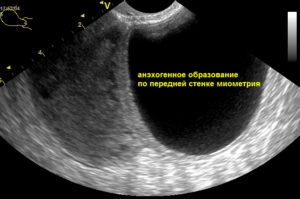

Анэхогенная структура, обнаруженная при проведении УЗИ, может быть лейомиомой. Проблема чаще диагностируется у женщин после 30 лет. В период менопаузы, беременности и грудного вскармливания миома может менять свои размеры, так как она зависима от гормонального фона пациентки.

Миомой матки называют доброкачественную опухоль, располагающуюся в полости детородного органа или за его пределами. Миома растет из срединного слоя матки – миометрия – и может достигать разных размеров, которые определяются неделями беременности.

Миома имеет диффузное или узловое расположение.

В последнем случае специалист при проведении сканирования видит анэхогенное включение. Отличить миому от кисты достаточно просто. Эта опухоль всегда имеет кровоснабжение, благодаря чему и развивается. В зависимости от расположения (внутри матки, в миометрии или за пределами детородного органа) опухоль может иметь индивидуальную симптоматику.

Большие размеры внутриполостных узлов становятся причиной бесплодия, периодических болей и прорывных кровотечений.